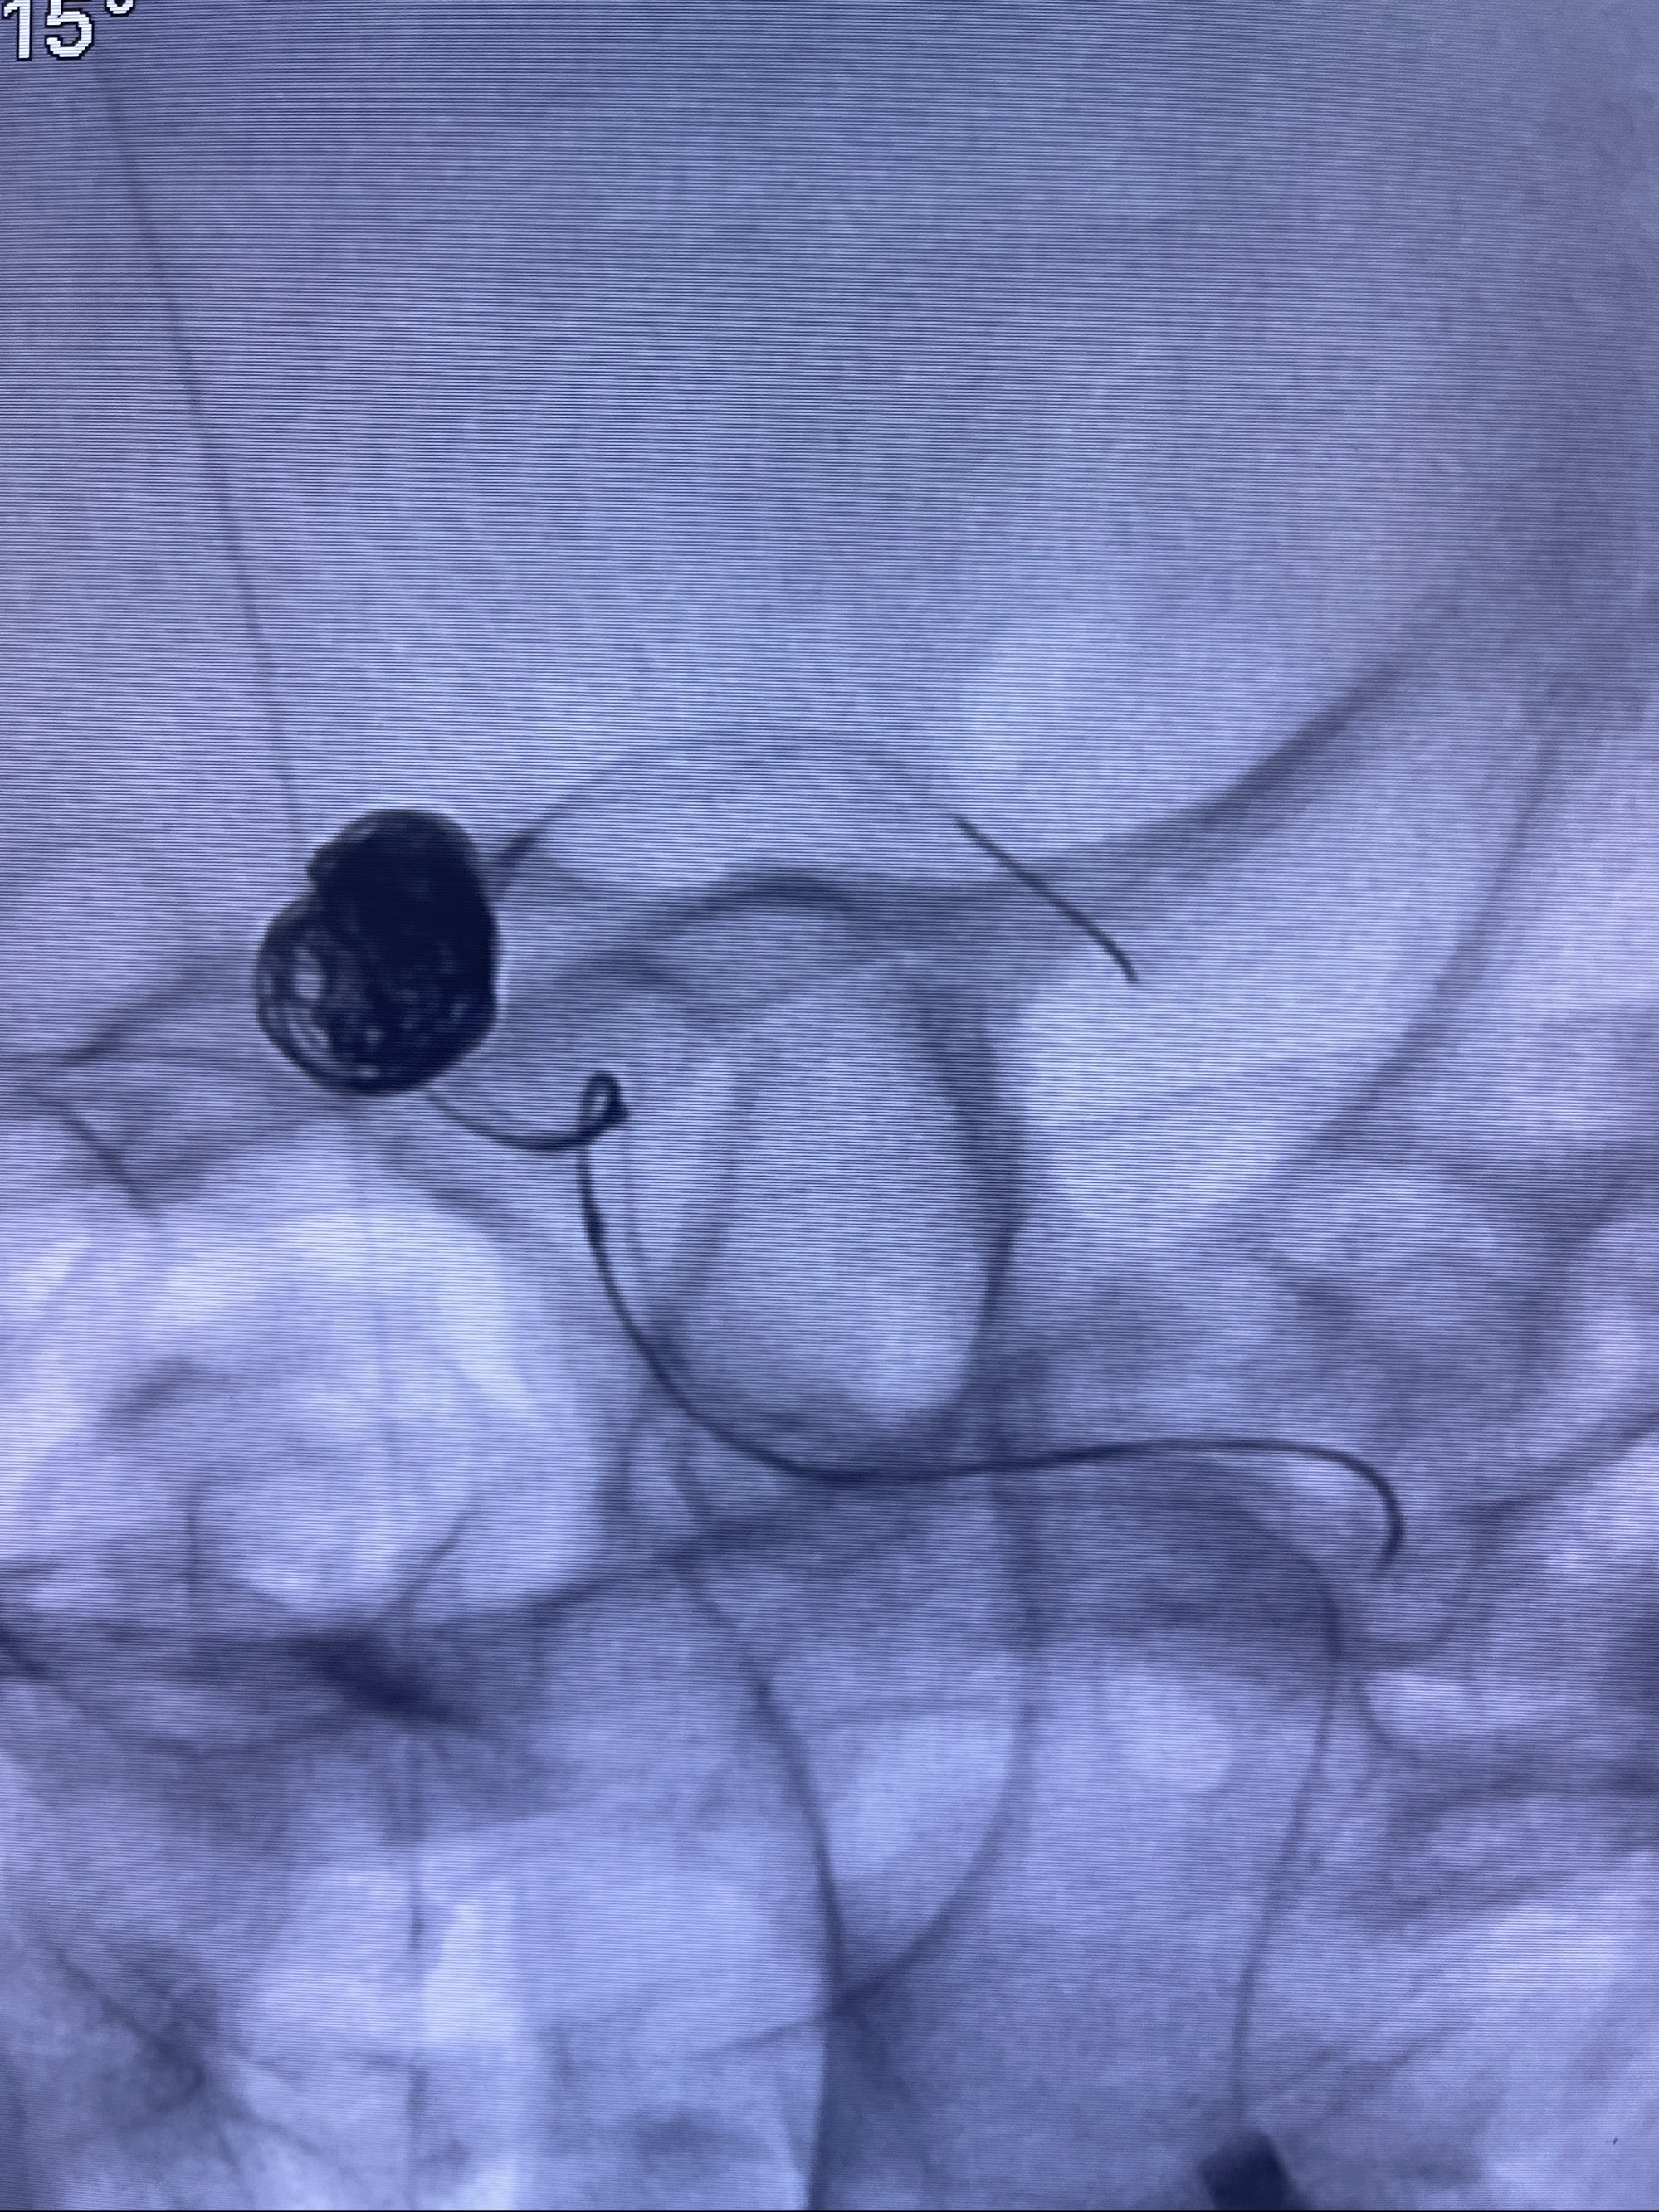

2023-08-30DSA:左侧颈内动脉眼动脉动脉瘤,约3*9.2*7.3mm大小

密网支架辅助栓塞

- Tubridge 4.0-20mm密网支架

- 加奇微弹簧圈:7*30/6*20/5*20/2*8